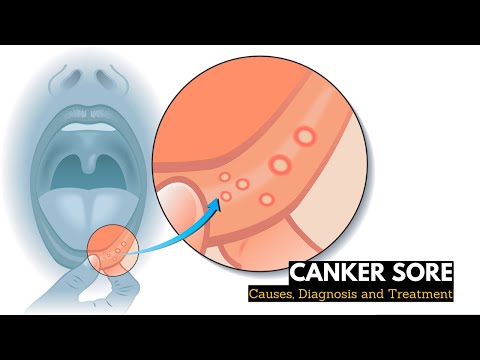

What is CANKER SORES? Causes, Signs and Symptoms, Diagnosis and Treatment.